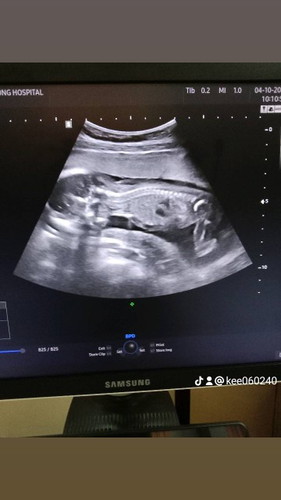

บ้านนี้21wยังไม่รู้สึกจริงจังเลยค่ะ แต่ไปซาวด์อาทิตย์ก่อนน้องเคลื่อนไหวบ่อยนะคะ แต่แม่น่าจะท้องหนาไม่รู้สึกเลยค่ะ

บ้านนี้หมอชมว่าดิ้นเก่งตั้งแต่13wแล้วคะแต่ยังไม่รู้สึกตอนนี้เริ่มแล้วคะได้21w+1

ท้องแรกบางคนจะรู้สึกได้ตอน 24 Weeks บ้านนี้ 19 weeks ยังไม่รฟุ้สึกเหมือนกันค่ะ